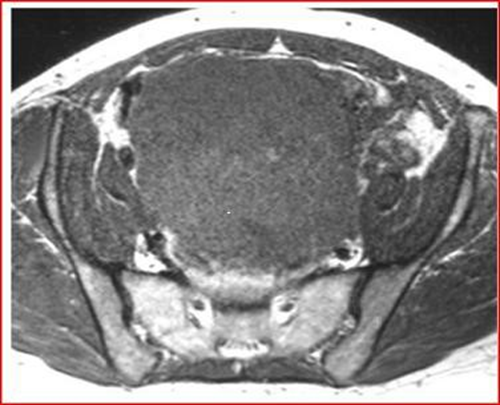

MRI shows a mass-free uterus, with no evidence of normal ovaries. The masses are approximately 13 cm in diameter and have low signal intensity on T1-weighted images and increased avidity after gadolin administration. On T2-weighted images the mass is hyperintense and the peripheral lesions probably correspond to ovarian follicles (Figures 4-6).

Figure 4: Axial T1-weighted MRI image, showing low signal intensity of the mass